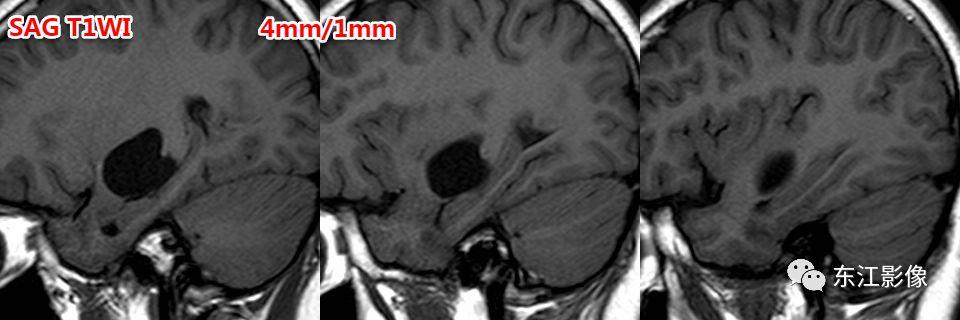

- 薄层扫描有助于这类小腔隙样灶的鉴别。

- 腔隙灶多为软化灶,FLAIR边缘多呈高信号,边缘不光整,无泪滴状或纺锤样外观。

前穿质区是血管周围间隙最常见的部位,主体位于脑实质,层面合适时可见尖角(==》多方位观察)。

矢状或冠状薄层图像更容易显示向下突出的“残留”的脑实质!这是区分两者的重要影像证据!

注意,3D TOF MRA有断层图像,也是薄层的3D 梯度回波T1W图像,尽管对比度较差,但有时候是可以提供帮助的!